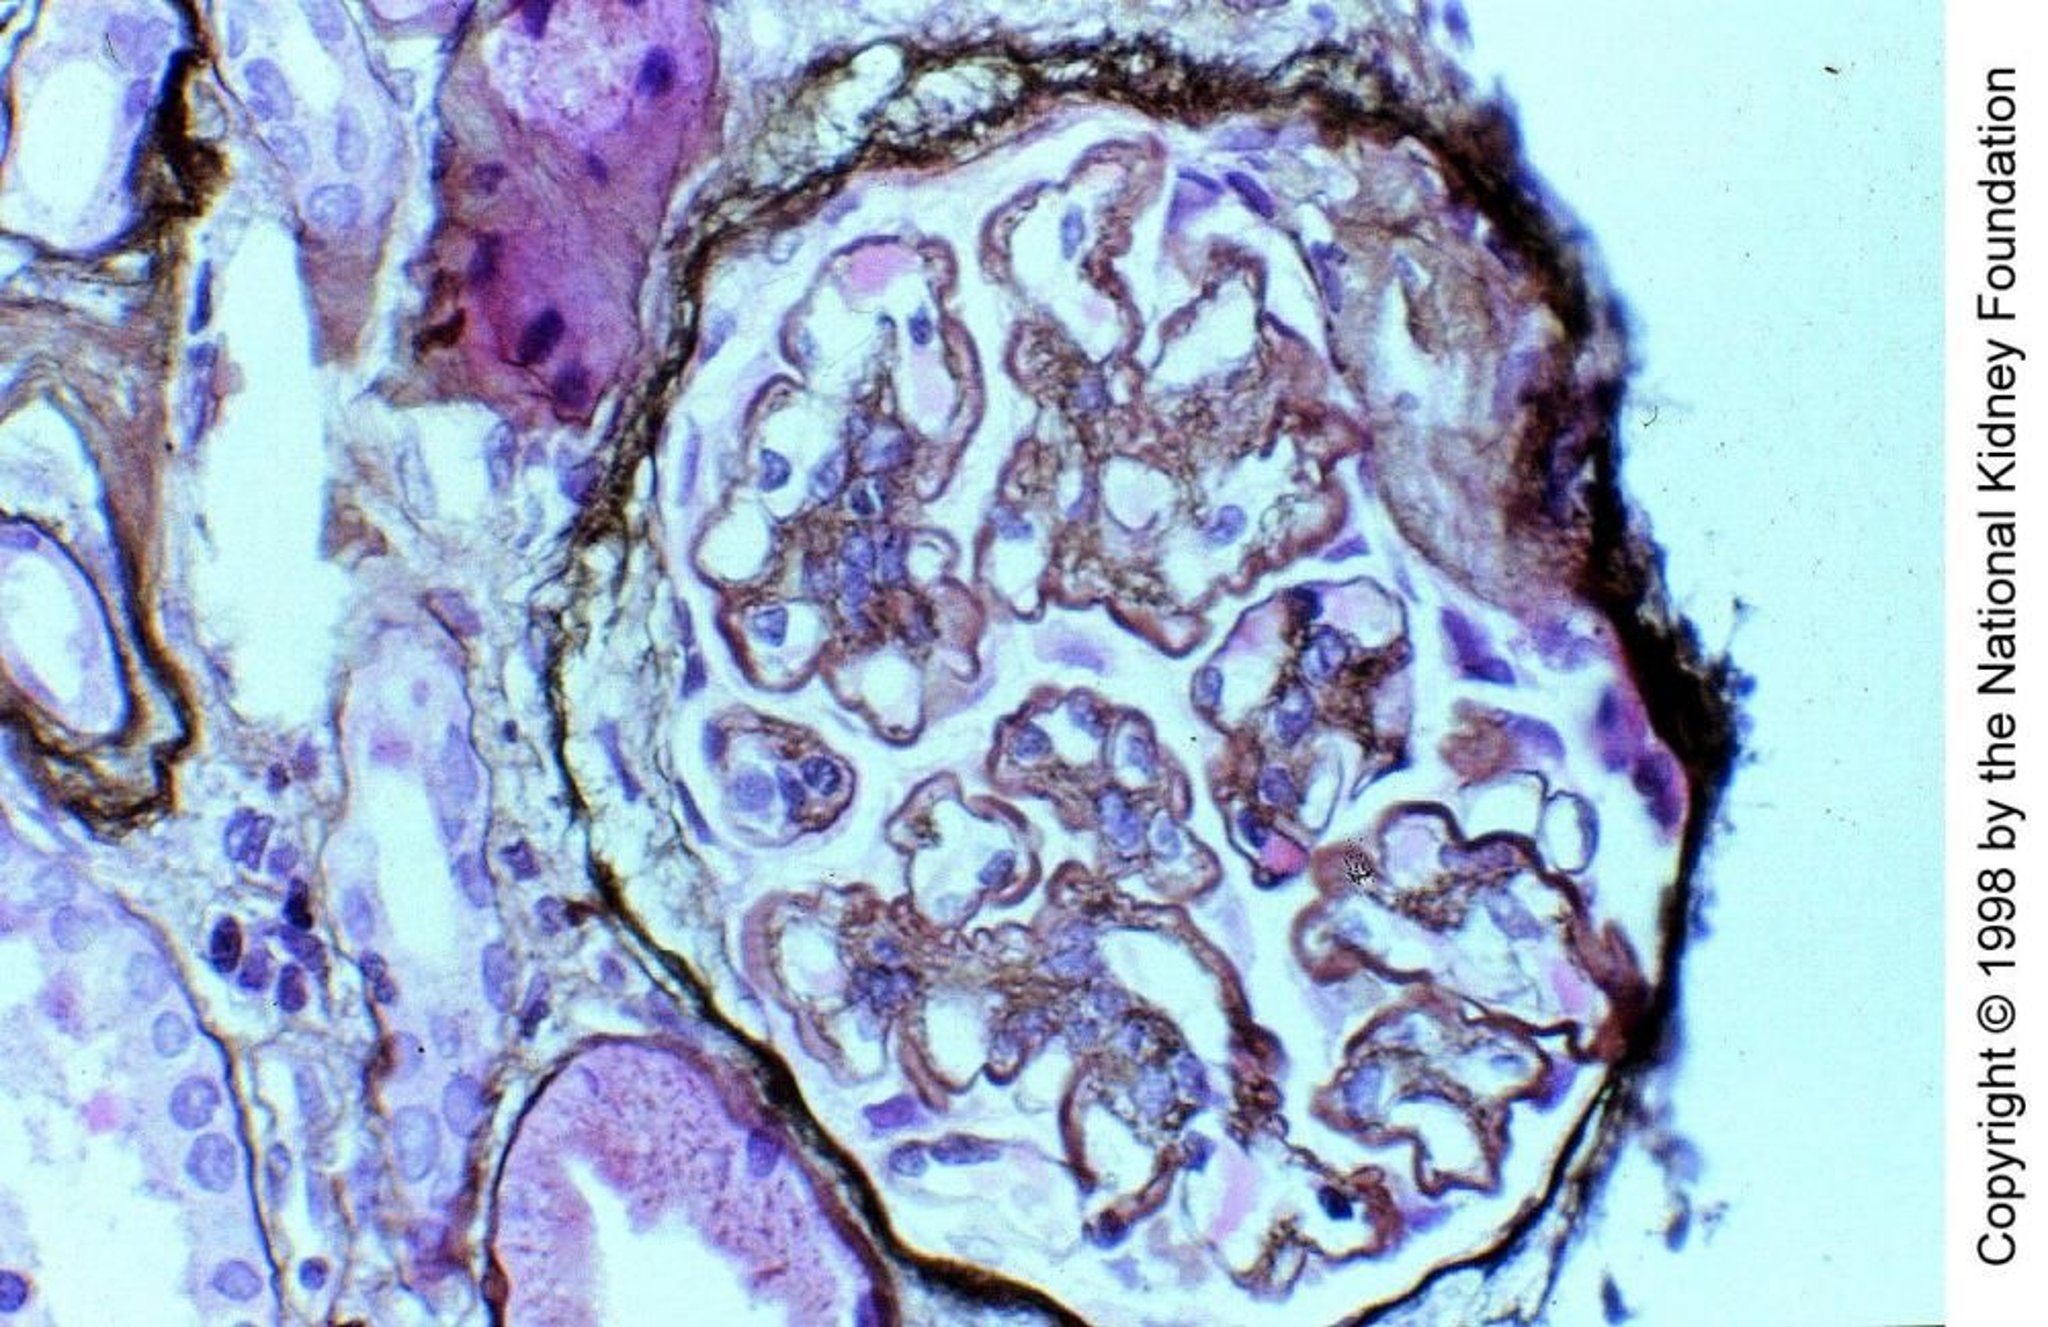

Glomérulonéphrite membranoproliférative, à médiation par le complément

Dans la glomérulonéphrite membranoproliférative de type II médiée par le complément, le facteur néphritique C3, un auto-anticorps IgG qui se comporte comme la névrine en clivant directement C3 en C3b, active le complément par la voie alternative dans les parois capillaires glomérulaires et le mésangium. Les dépôts de C3 remplacent partiellement la membrane basale de la lamina densa, lui donnant un aspect de ruban épaissi et caractéristique (coloration de Jones à l'argent, ×400).

Image fournie par Agnes Fogo, MD, and the American Journal of Kidney Diseases' Atlas of Renal Pathology (voir www.ajkd.org).